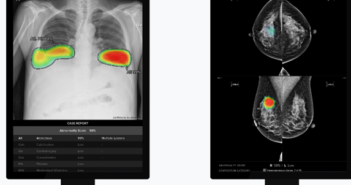

의료 인공지능(AI) 기업 루닛이 최근 대만 중산의과대학 및 싱가포르 대형병원에 암 진단을 위한 AI 영상분석 솔루션을 공급하는 계약을 체결했다고 11일 밝혔다. 루닛은 대만 항구도시 가오슝에 위치한 ‘중산의과대학교(Chung Shan Medical University)’ 연구팀의 폐암 진단 연구 프로젝트에 흉부 엑스레이 AI 영상분석 솔루션 ‘루닛 인사이트 CXR’을 공급한다. 현재 대만의 국가 폐암검진은 흡연자, 가족력 보유자 등 주로 고위험군을 대상으로만 제한적으로 진행되며, LDCT(저선량 컴퓨터단층촬영) 방식을 사용하고 있다. 이번 연구에서는 흉부 엑스레이에 AI를 활용한 검진 방식이 기존 대비 검진 범위를 확대하고, 비용 효율성과 정확도를 높일 수 있을지 검증할 계획이다. 연구가 성공적으로 수행되면 현지 의료계 및 사회적으로도 긍정적인 파급력을 가져올 것으로 기대된다. 아울러, 루닛은 싱가포르 대형병원 ‘글렌이글스(Gleneagles)’와 유방촬영술 AI 영상분석 솔루션 ‘루닛 인사이트 MMG’ 공급 계약을 체결했다. 글렌이글스 병원은 동남아시아 최대 규모 병원 그룹인 ‘파크웨이 판타이(Parkway Pantai, Ltd., 이하 파크웨이 그룹)’에 속해 있다. 파크웨이 그룹은 말레이시아, 홍콩, 인도, 중국 등지에 중대형 규모 병원 20곳 이상을 운영 중이다. 이번 계약은 보건복지부 산하 보건산업진흥원이 진행하는 ICT기반 의료시스템 해외진출 지원사업의 일환으로 체결됐다. 루닛은 이번 계약을 통해 파크웨이 그룹 내 다른 병원으로의 공급도 추진할 계획이며, 파크웨이 그룹이 가진 네트워크와 파급력을 고려할 때 중화권 및 아세안 시장에 의료 AI 기술의 활용과 발전을 촉진하는 계기가 될 것으로 기대된다. 서범석 루닛 대표는 “중화권과 아세안 국가에서는 첨단 의료 서비스 및 진단 정확성, 고효율 의료 솔루션에 대한 수요가 꾸준히 증가하고 있다”며 “이번 대만 및 싱가포르향 공급 계약은 해당 지역에 대한 사업 확장에 중요한 발판이 될 것으로 기대한다”고 말했다. 관련 기사 더보기 https://www.venturesquare.net/915260